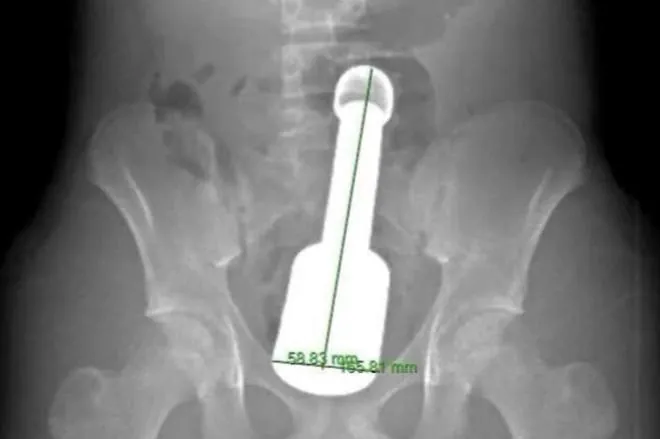

18cm 절구공이 항문에 박혀 입원한 베트남 15세 소년

아…안차가웠으려나 근데 두께랑 길이는 대체 왜 써놬ㅋㅋ